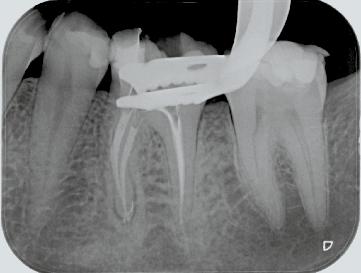

FQ . Clinical Case.

Dr. David Christofzik Specialist for endodontics and traumatology, Kiel /Germany

Rafael Michiels

for endodontics

“FQ allows general practitioners to proceed with a great deal more security and confidence, whereas the high versatility of the instruments enables specialists to respond individually to complicated canal anatomies, as shown in the patient case.”